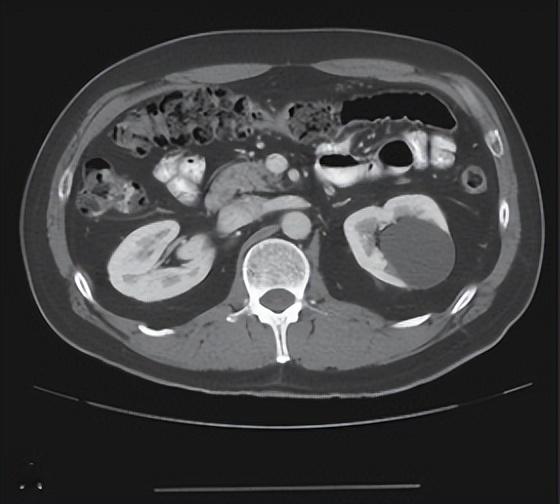

肾囊肿Bosniak分级意义及处理

Bosniak分级系统最初由美国放射学家Martin Bosniak于1986年提出,旨在通过CT影像特征对肾脏囊性病变进行分类。该系统将病变分为Ⅰ~Ⅳ级,其中Ⅰ级为单纯性囊肿,恶性风险几乎为零;Ⅱ级为复杂囊肿,恶性风险较低;Ⅲ级为可疑恶性;Ⅳ级则高度怀疑恶性。这一分类方法为临床医生提供了判断肾脏囊性病变良恶性的标准,大大提高了诊断的准确性和一致性。